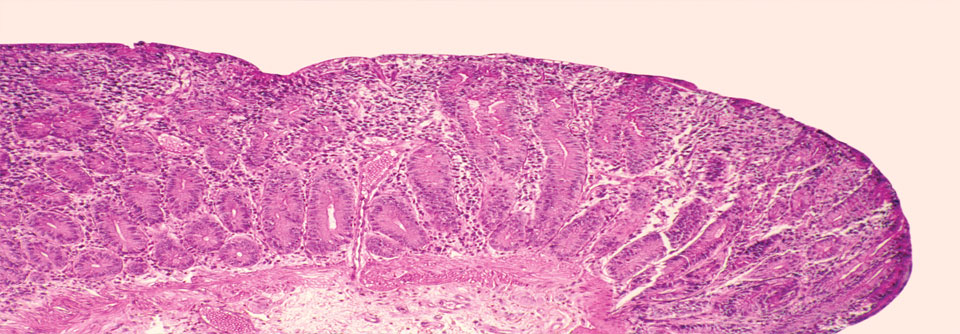

Das höhere Sterberisiko bei Zöliakiepatienten könnte auf chronische Entzündungsprozesse zurückzuführen sein. Das höhere Sterberisiko bei Zöliakiepatienten könnte auf chronische Entzündungsprozesse zurückzuführen sein. © iStock/MarsBars

Der Gastroenterologe Professor Dr. Benjamin­ Lebwohl­ von der Columbia University in New York und seine Kollegen haben die Gesamt- sowie die ursachenspezifische Mortalität einer Kohorte von nahezu 50 000 Schweden analysiert. Bei diesen war zwischen 1969 und 2017 anhand von Dünndarmbiopsien die Diagnose Zöliakie gestellt worden. Die Vergleichsgruppe bildeten knapp 246 500 Kontrollen aus der Allgemeinbevölkerung.